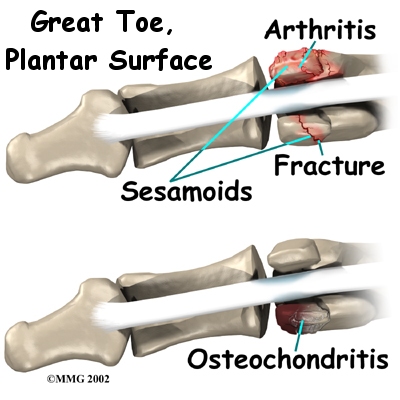

Fractures can also cause pain in the sesamoids. Fractures can occur when a person falls and lands bluntly on the ball of the foot. Stress fractures can also occur in the sesamoid bones. Stress fractures are usually caused by the strain of overworking the soft tissues. Athletes most often suffer stress fractures of the sesamoids because of the heavy and repeated demands that training places on the soft tissues of the foot and big toe.

Fractures can also cause pain in the sesamoids. Fractures can occur when a person falls and lands bluntly on the ball of the foot. Stress fractures can also occur in the sesamoid bones. Stress fractures are usually caused by the strain of overworking the soft tissues. Athletes most often suffer stress fractures of the sesamoids because of the heavy and repeated demands that training places on the soft tissues of the foot and big toe.

Arthritis can develop where the sesamoids glide under the bone of the big toe. The sesamoid bones create a joint where they move against the bone of the big toe. Like other joints in the body, this joint can also develop arthritis. Arthritis is more likely to be a problem in people who have high arches in their feet. The high arch causes the main joint of the big toe to become rigid. This focuses strain and pressure on the sesamoids.

In some cases, blood supply to the sesamoid bone is decreased. This condition is called . Osteochondritis causes a piece of the bone to actually die. The body's attempts to heal the area may build up extra calcium around the dead spot.

Fractures can also cause pain in the sesamoids. Fractures can occur when a person falls and lands bluntly on the ball of the foot. Stress fractures can also occur in the sesamoid bones. Stress fractures are usually caused by the strain of overworking the soft tissues. Athletes most often suffer stress fractures of the sesamoids because of the heavy and repeated demands that training places on the soft tissues of the foot and big toe.

Fractures can also cause pain in the sesamoids. Fractures can occur when a person falls and lands bluntly on the ball of the foot. Stress fractures can also occur in the sesamoid bones. Stress fractures are usually caused by the strain of overworking the soft tissues. Athletes most often suffer stress fractures of the sesamoids because of the heavy and repeated demands that training places on the soft tissues of the foot and big toe.